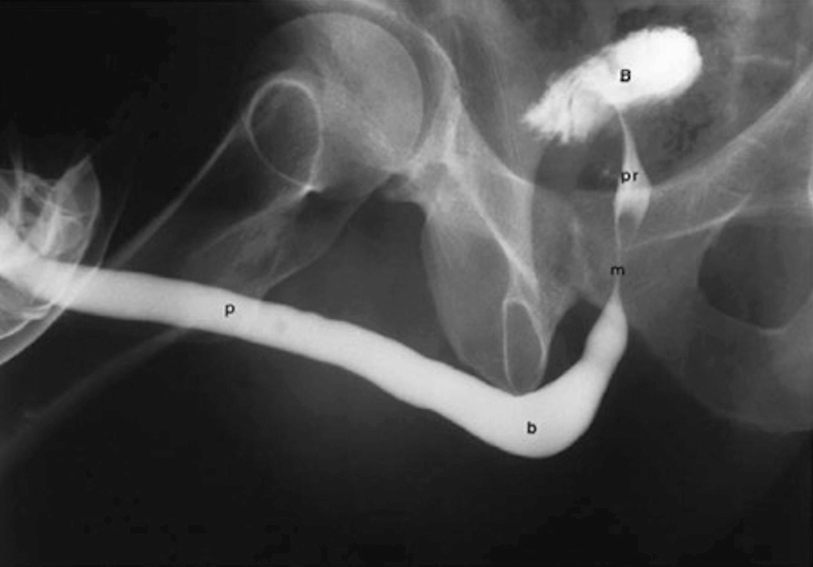

5.3.2 Retrograde Urethrogram and Voiding Cystourethrogram

A properly performed and normal retrograde urethrogram . The four distinct parts and bladder are labelled accordingly: p = penile urethra, b = bulbar urethra, m = membranous urethra, pr = prostatic urethra, b = bladder